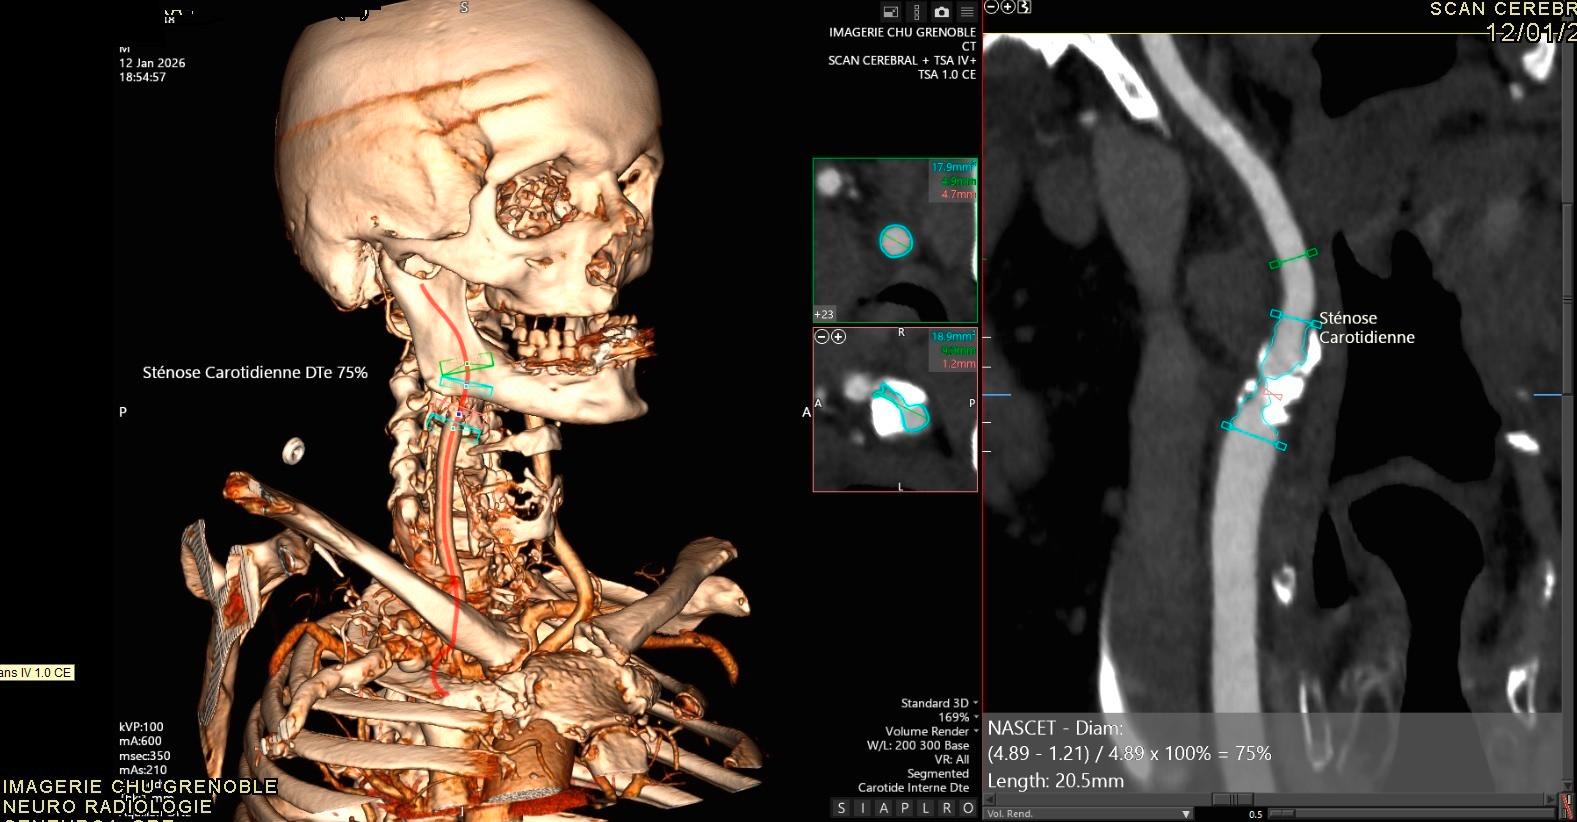

Très à la pointe depuis plusieurs années en matière de protocoles de coopération en imagerie, le CHU de Grenoble a mis en place il y a quelques mois un nouveau dispositif qui permet aux manipulateurs radio de réaliser des mesures au scanner de neuroradiologie pour l'hématome intracérébral, la sténose carotidienne et l'anévrisme cérébral.

Pour mettre en place ce protocole, l’équipe a monté un dossier et l’a présenté à la commission médicale d’établissement (CME) en juin 2025. L’activité a ensuite démarré au mois de septembre. Le service compte 18 manipulateurs radio et tous participent à ce protocole de coopération. « Tous les manipulateurs qui font du scanner ont été volontaires pour participer, donc ils ont tous été inclus dans le protocole car il faut que tout le monde puisse faire les mesures à l'instant T quand le médecin en a besoin », explique Jérôme Gouye, l’un des manipulateurs de l’équipe.